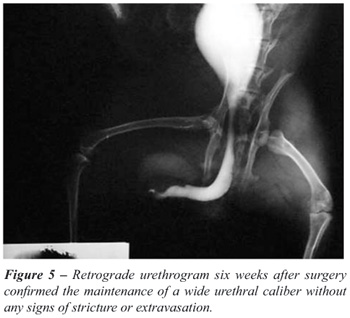

The typical squamous epithelium of buccal mucosa and minimal inflammatory cell infiltration in the subepithelial tissues were observed in all rabbits at the grafted buccal mucosa six weeks after surgery. Minimal fibrosis was observed. Microscopically the junction of the graft and normal urethra was identifiable in all groups. Six weeks after surgery retrograde urethrograms confirmed the maintenance of a wide urethral caliber without any signs of stricture or extravasation (Figure-5).